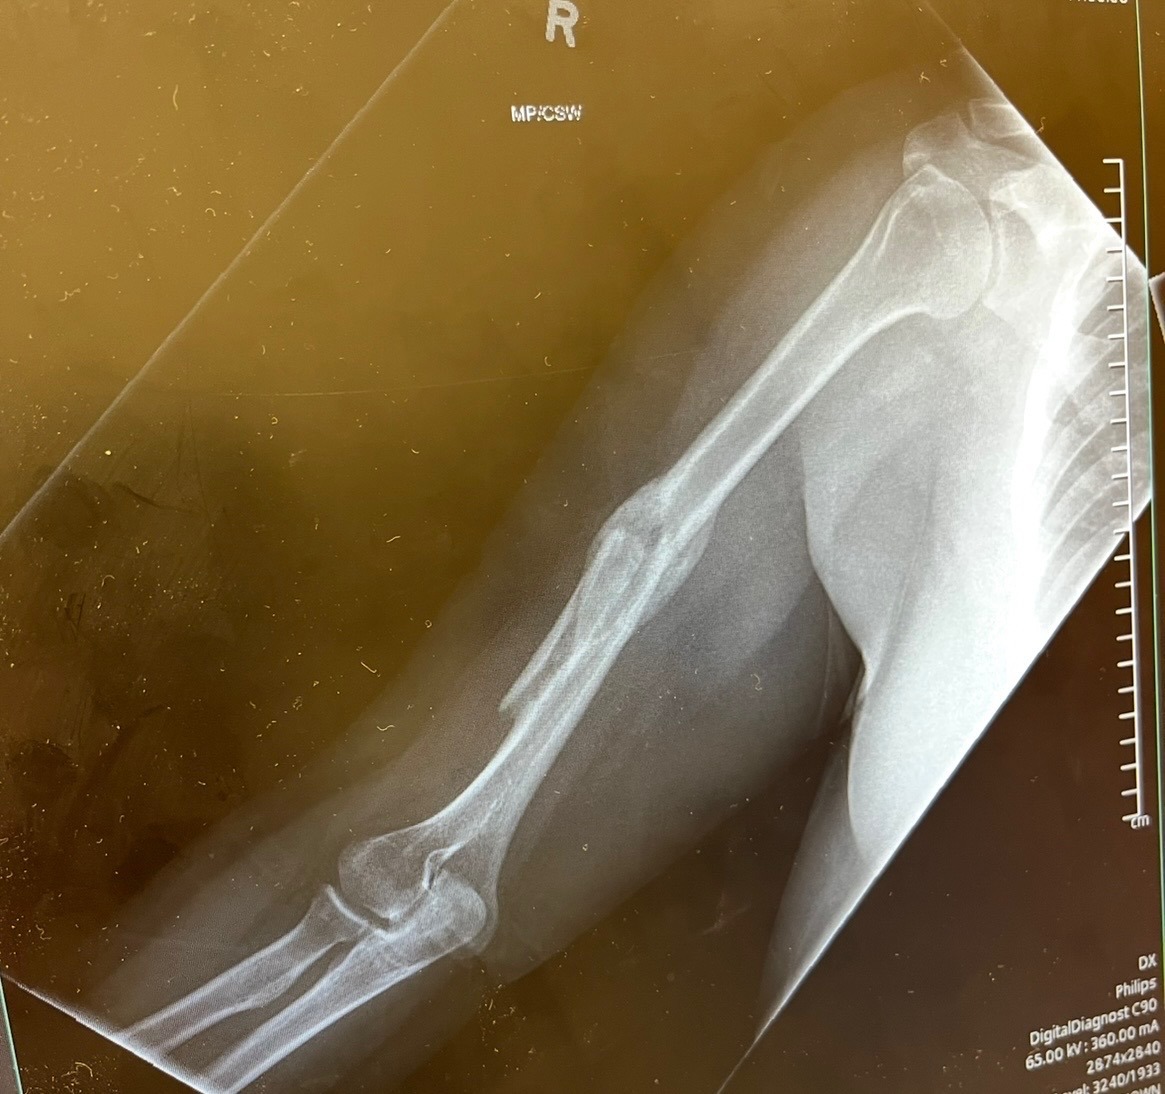

On November 23rd, 2025, my sister Rebekah Stevenson was in a traumatic car accident that changed her life. Her vehicle ran off the road and into a ditch, leaving her trapped and injured for five days before she was finally found by a man walking his dog. During this time, Rebekah suffered a broken right arm, three broken ribs, multiple broken and knocked-out teeth, and a shattered foot. She underwent surgery to repair her foot on January 13th, 2026, and spent just over four weeks in the VA hospital. Now, she is learning to walk again with a walker and a medical boot, showing incredible strength and determination every day.